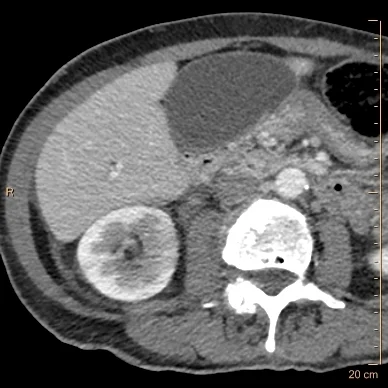

Conventional CT shows subtle hypoperfusion in the right kidney medially. Note the gallbladder looks normal.